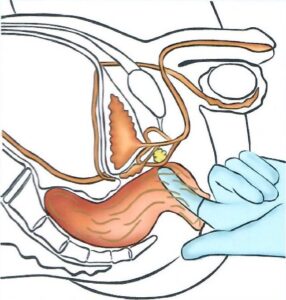

ESPLORAZIONE RETTALE

ESPLORAZIONE RETTALE

L'esplorazione rettale è una vecchia, ma sempre consigliabile, manovra diagnostica che dà informazioni preziose sullo stato, le dimensioni e sui rapporti della prostata con gli organi vicini.

E' possibile, con questo semplice atto, diagnosticare delle prostate ingrossate in modo benigno, infiammate o anche tumorali.

Oggi, di fronte a valori del PSA superiori a 4 pur in presenza di un'esplorazione rettale negativa, solitamente si deve effettuare un'ecografia transrettale con biopsie multiple.

Tale esame viene condotto esclusivamente dallo specialista urologo.